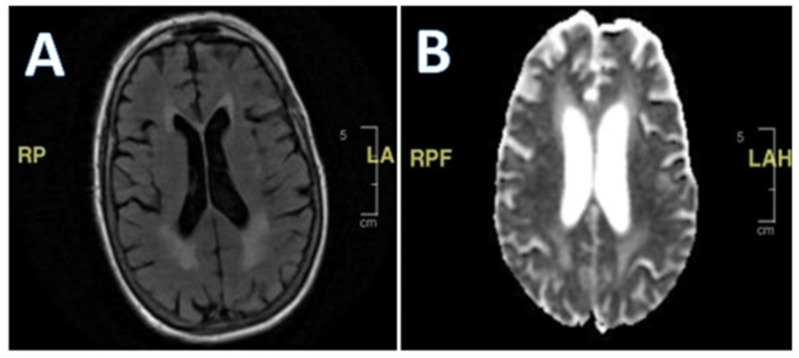

Background/Objectives: Lower-extremity weakness in older adults is often overlooked, yet it can have reversible or medical causes that contribute to increased falls. Common factors include vision disturbances, impaired balance due to otolith dysfunction, arthritis-related immobility, and lower-extremity neuropathy. This case presents a unique diagnostic challenge in evaluating bilateral lower-extremity weakness and recurrent falls in an older adult, highlighting the complexity of diagnosing conditions with overlapping symptoms. Case Presentation: The patient, a woman with a history of a neuroendocrine tumor, experienced progressive weakness in her lower extremities, along with oculomotor and facial muscle involvement, despite extensive testing. Key clinical findings included elevated protein levels in cerebrospinal fluid, suggesting the possibility of an infectious or autoimmune process. A thorough investigation was conducted, including testing for both common and rare conditions such as Guillain-Barré syndrome, Lyme disease, and tuberculosis. Results: Despite comprehensive diagnostic efforts, no clear etiology was identified. The patient's condition was eventually considered to be related to carcinomatosis meningoencephalitis, a rare complication from a previous cancer diagnosis. Given the progressive nature of her symptoms and lack of treatment options, she was transitioned to palliative care. Conclusions: This case highlights the importance of a comprehensive differential diagnosis in older patients with unexplained weakness and falls. Rare neurological conditions should not be overlooked, even when more common causes are suspected. Clinicians should remain aware that falls and weakness in older adults may stem from various pathologies, some of which are reversible if identified early, and rare causes must always be considered when standard treatments fail.